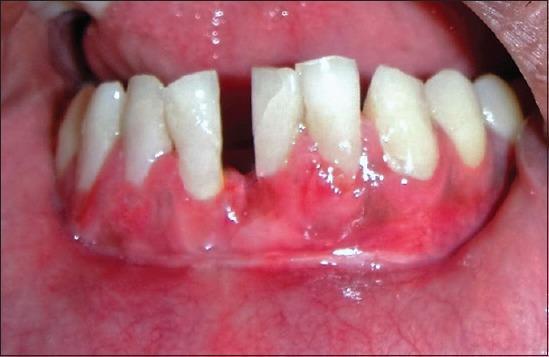

Miller's class III gingival recession is a common entity observed in individuals, posing a difficult situation for the clinicians to treat. Large fenestration defects with cervical abrasion compromise the esthetics resulting in poor prognosis. Obtaining predictable and esthetic root coverage has become an integral part of periodontal therapy. The present case report describes a situation where class III gingival recession with cervical abrasion was seen in the lower central incisors. The patient was successfully treated with a combination of restorations (Filtek Z350(®) composite resin) to fill the defect, followed by fenestration procedure to increase the vestibular depth and subsequently with grafting procedure (soft tissue autograft with bovine-derived xenograft collagen [Bio-oss]). Though the results were not tangible esthetically, it was functionally successful as evidenced during the follow-up period.

米勒Ⅲ类牙龈退缩在个体中很常见,给临床医生的治疗带来难题。伴有颈部磨损的大穿孔缺损会影响美观,导致预后不良。获得可预测且美观的牙根覆盖已成为牙周治疗不可或缺的一部分。本病例报告描述了在下颌中切牙出现Ⅲ类牙龈退缩伴颈部磨损的情况。患者通过联合修复(Filtek Z350®复合树脂)填充缺损、开窗手术增加前庭深度,随后进行植骨手术(自体软组织移植联合牛源异种移植胶原蛋白[Bio-oss])成功得到治疗。尽管在美观方面效果不明显,但在随访期间证明功能上是成功的。